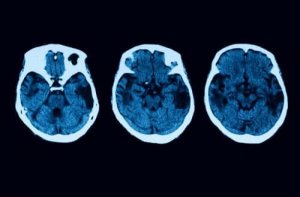

Jednak testy diagnostyczne na tym się nie kończą. Aby wyjaśnić wszelkie wątpliwości, zostaną przeprowadzone inne testy neurologiczne, takie jak MRI i tomografia. Jeśli wszystkie wyniki będą wskazywać na to, że cierpisz na zanik korowy tylny, będziesz mógł wybrać różne metody leczenia.